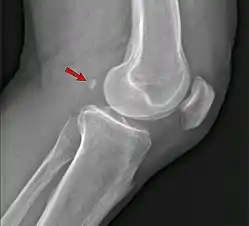

Os ulnostyloideum

The os ulnostyloideum is an ulnar styloid process that is not fused to the rest of the ulna bone.[6] On X-rays, an os ulnostyloideum is sometimes mistaken for an avulsion fracture of the styloid process. However, the distinction between these is extremely difficult.[6][7] It is alleged that the os ulnostyloideum has a close relationship with or is synonymous with the os triquetrum secundarium.[8]